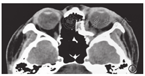

患者女,21岁。因"左眼车祸伤后视物重影半个月"就诊于北京大学第三医院。眼科检查:右眼视力1.0,左眼视力0.8,眼压:右眼13.5 mmHg,左眼10.6 mmHg(1 mmHg=0.133 kPa)。眼球突出度:右眼13.0 mm,左眼11.0 mm,眶距97.0 mm,左眼下转、外转运动受限,眼睑轻度肿胀,结膜稍充血,角膜透明,KP(-),前房中等深,前房闪光(-),瞳孔圆,直径约3.0 mm,直接及间接对光反应正常,晶状体透明,玻璃体透明,眼底未见明显异常。眼眶CT示:左眼眶下壁、内壁骨折。于全麻下行左眶壁骨折整复术,术中显露眶壁骨折窗,松解剥出嵌入组织,此时可见左侧瞳孔较右侧略大,植入预成形钛金属网,术后左眼加压包扎、监测光感,口服强的松30 mg 1次/d,共3 d,术后2 d打开绷带,患者诉左眼视物模糊,眼科检查:左眼视力0.5,左眼睑轻度肿胀,下转、外转运动受限,结膜充血水肿(+),角膜透明,前房中等深,瞳孔散大,直径约8 mm,直接、间接对光反应迟钝,近反应存在,余眼内未见明显异常。因患者术前瞳孔、视力正常,故考虑可能钛网位置偏深压迫视神经,即刻复查眼眶CT(图1)见钛网位置太深,进行左眼钛网调位,术中调整钛网后左眼瞳孔缩小至4 mm,右侧瞳孔此时3 mm,但术后1 d查体见左眼瞳孔仍大,住院期间可见左眼瞳孔逐渐缩小,但仍较正常大,予口服强的松30 mg 1次/d、甲钴胺0.5 mg 1次/d,1周后视力恢复至0.8,瞳孔为8 mm。术后40 d复查左眼瞳孔逐渐变小约6 mm(图2A)。6个月时患者左眼视野正常,视力恢复至术前,瞳孔逐渐缩小至4 mm,直间接光反应灵敏,与对侧对称出现。术后8个月裂隙灯显微镜下双侧瞳孔等大,但日光下左侧瞳孔仍为4 mm,右侧瞳孔此时为3 mm(图2B)。